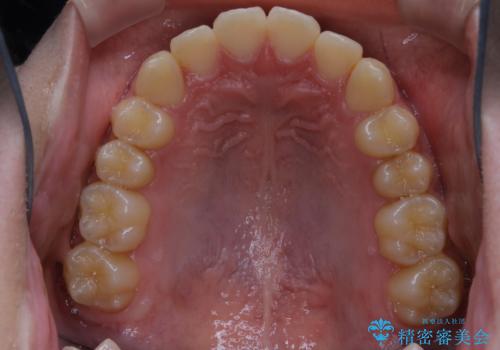

非抜歯で劇的に出っ歯を改善!インビザラインとカリエールの組み合わせ治療

- 患者様、出っ歯のお悩みで来院されました。

骨格の分析を行ったところ上顎も出てはいるのですが、下顎が引っ込んでいる状態であるということがわかりました。

よって上顎の歯を抜いて治療をするのではなく、カリエールという器具を使用して下顎を前に引っ張り出しながら上顎を引っ込めるという治療を行うことにしました。